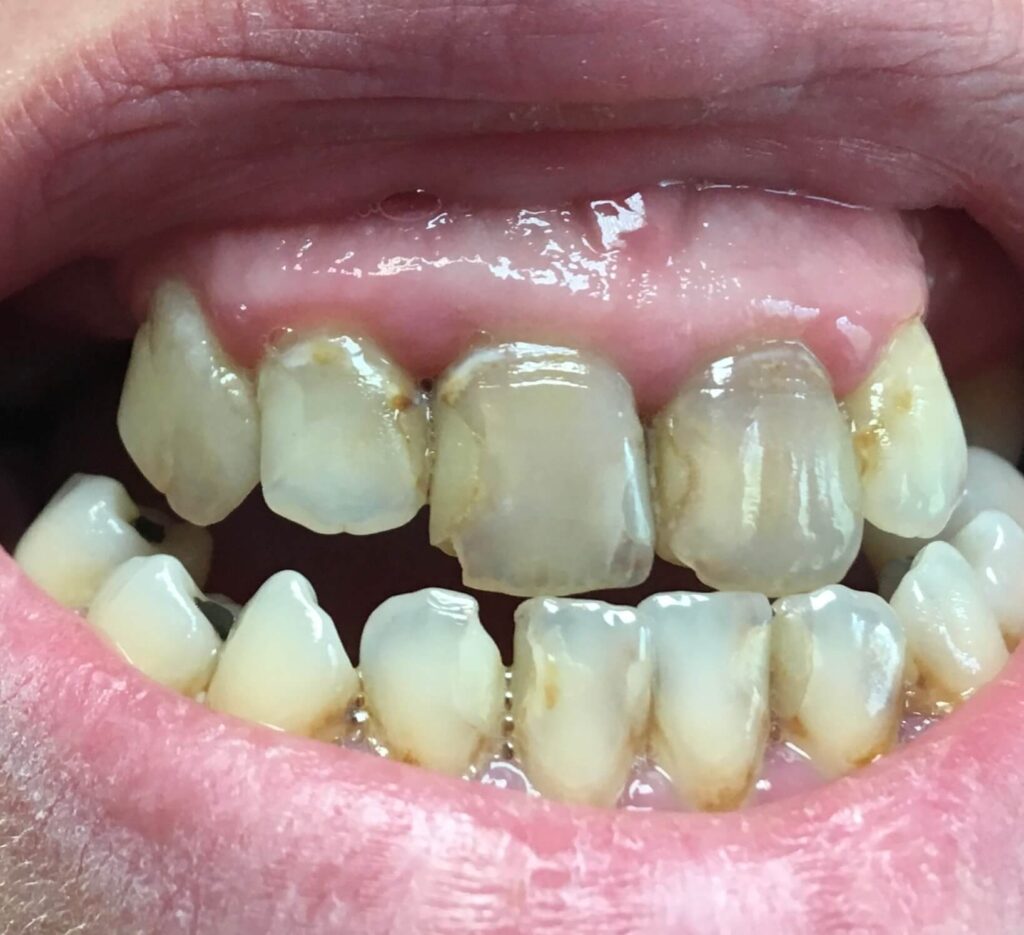

Każdy uśmiech ma swoją historię – my pomagamy ją opowiedzieć na nowo. Dzięki indywidualnie dobranym planom leczenia przywracamy pacjentom nie tylko piękny wygląd zębów, ale również komfort i funkcjonalność w codziennym życiu. Poniżej przedstawiamy wybrane przypadki metamorfoz, które pokazują, jak zaawansowana protetyka, nowoczesne techniki odbudowy oraz precyzyjne leczenie endodontyczne potrafią całkowicie odmienić uśmiech.